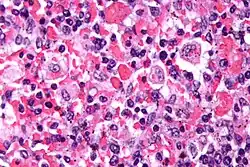

Micrograph showing red blood cells within macrophages. H&E stain.

Light microscopic image of bone marrow showing stromal macrophages containing numerous red blood cells in their cytoplasm

The blood count typically shows decreased numbers of blood cells—including a decreased number of circulating red blood cells, white blood cells, and platelets. The bone marrow may show hemophagocytosis. The liver function tests are usually elevated. A low level of the protein albumin in the blood is common.